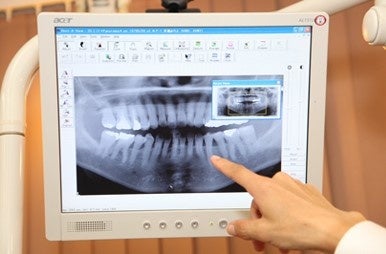

2. パノラマレントゲン検査

パノラマレントゲン検査パノラマレントゲン検査

パノラマレントゲンで撮影を行い、虫歯や歯周病の状態を詳細に把握し、ご説明いたします。

※ご希望の方には特別価格、別途5,500円(税込)でCT撮影を行います。